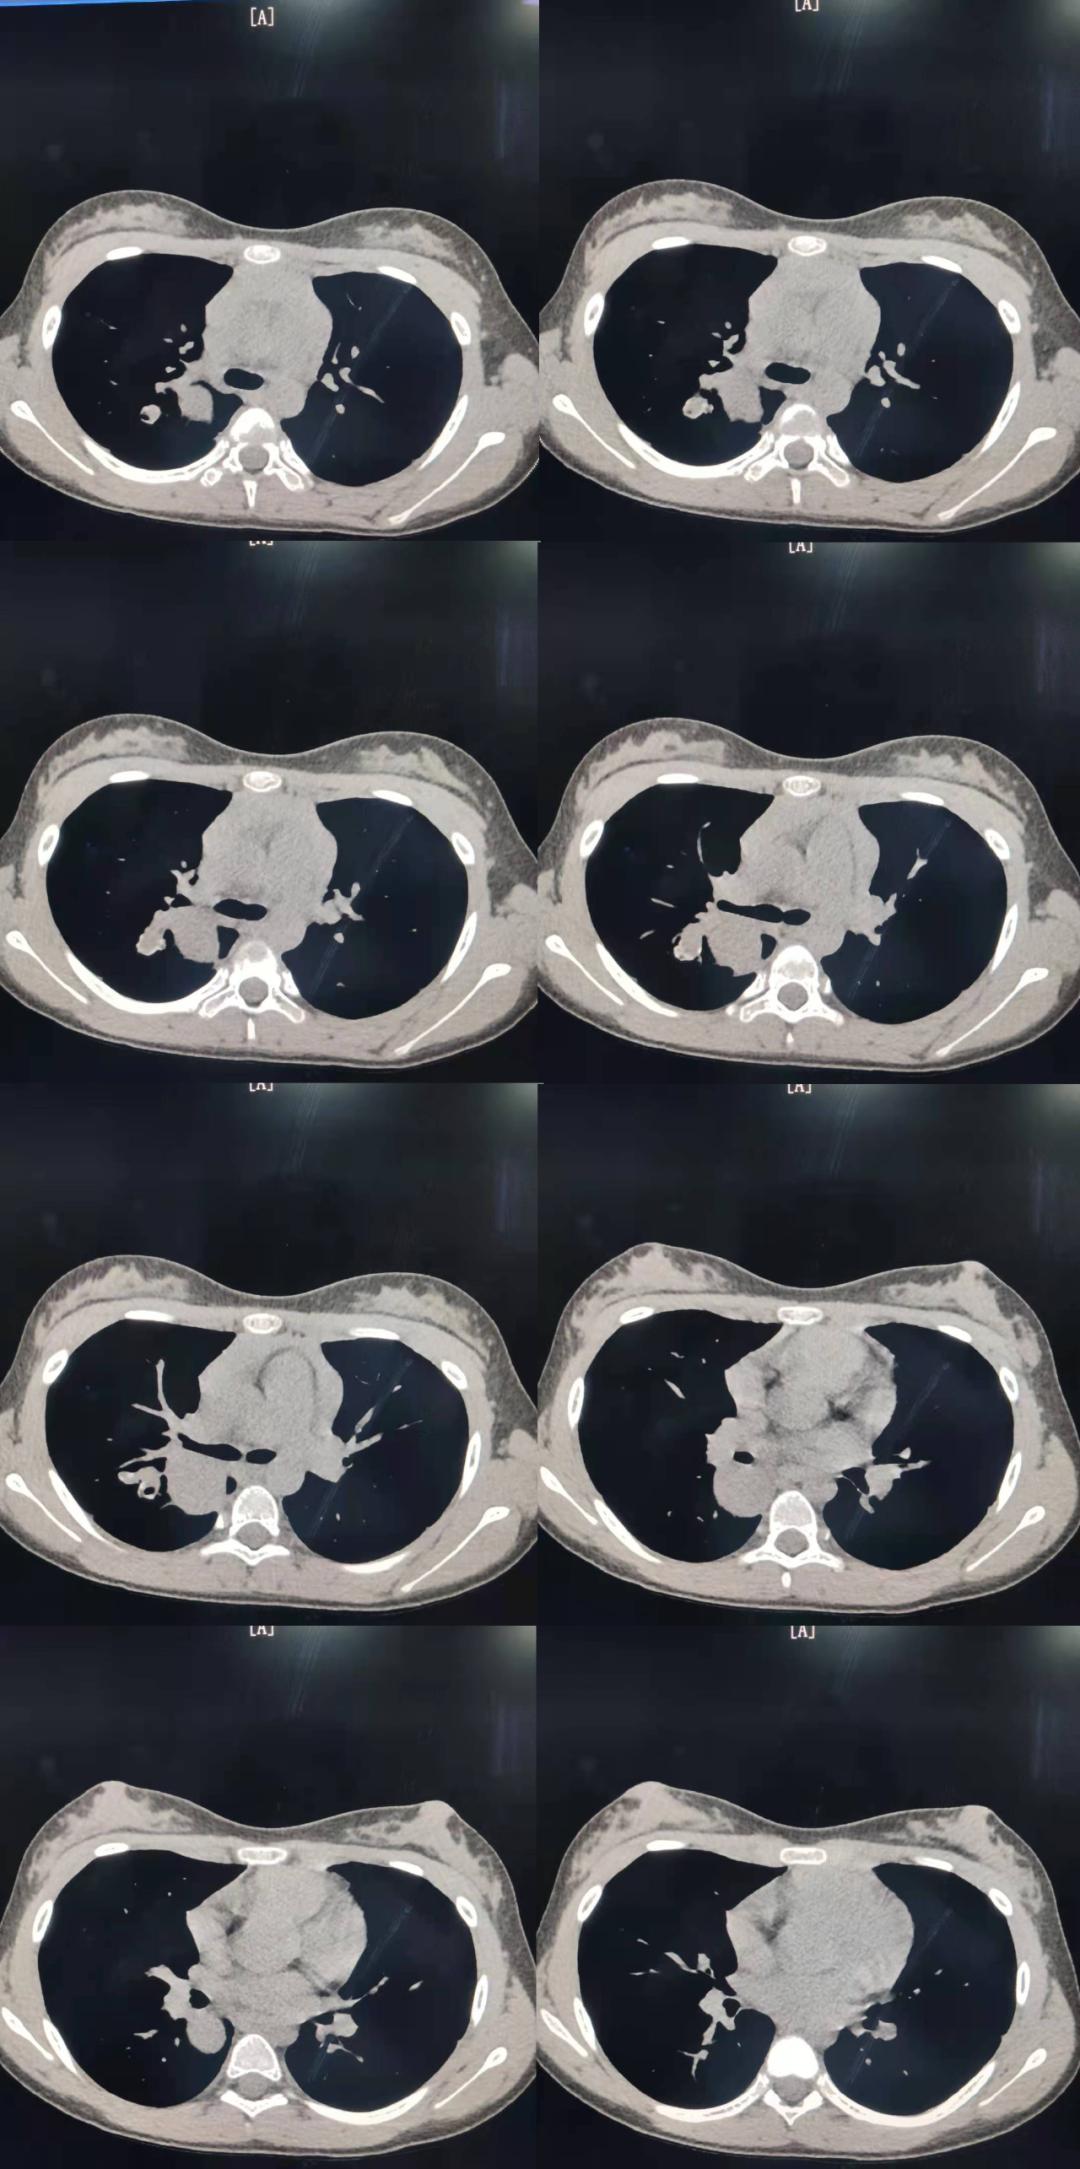

女性 13 岁 因发热、胸闷一周入院检查;一周前受凉发热后出现发热,最高体温达 38.4°,伴活动后胸闷,休息片刻可缓解;胸部 CT 平扫+增强图像如下;

患者 13 岁小孩 女性 因发热入院,发现右肺上叶近肺门处椭圆形肿块,密度相对均匀,增强扫描未见明显强化,这种影像表现我们可以考虑哪些疾病呢?我相信第一个就会考虑支气管囊肿,因为病灶椭圆形、边界清晰,没有强化,从影像表现上来看,确实首先应该考虑。

一、肺实质内型最常见,一般没有症状,表现为圆形或类圆形肿块,边界清晰,边缘光滑或浅分叶,病变内可以出现脂肪成分、爆米花样钙化,此影像表现较为特异,但是有一般以上的病例没有脂肪也没有钙化,估给诊断带来困难,增强扫描一般均无明显强化表现。